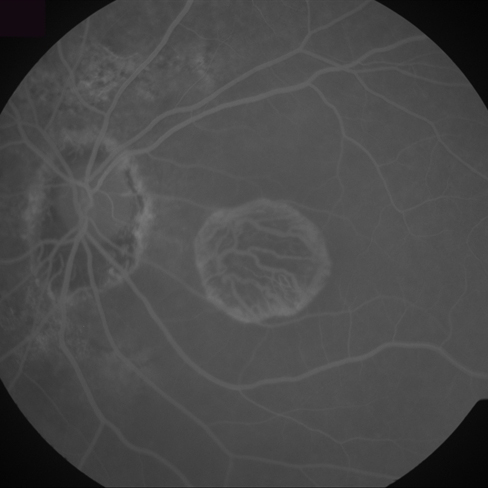

Figure 6: Three FA fundus images with symptom of drusen and corresponding generated images. (a), (b), (c) Original images. (d), (e), (f) Generated images.

Furthermore, generated images from FA images are presented in Fig. 6 and Fig. 7. Results in the images are nearly identical to the original images, because original networks are applied to stylize color images. However, six generated images contain more concise features than the original ones, which helps ophthalmologists make better judgments. Therefore, this style transferring networks can fulfill edge sharpening and enhancement of contrast. No matter which kinds of images are generated, advanced features in new disease images still exist. Furthermore, analyses of image performance by EyeNet and CAMs for prediction are presented in a later section.